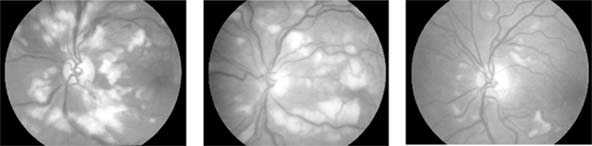

Figure 15-4: Cotton-wool spots. Numerous cotton-wool spots are seen in the posterior poles in three patients. Left: A young woman with acute systemic lupus erythematosus and neurologic disease. Center: A young man with pancreatitis. Right: A patient with AIDS. Cotton-wool spots resolve over 6 weeks regardless of their cause.

Figure 15-4

The appearance of the fundus in hypertensive retinopathy is determined by the degree of elevation of the blood pressure and the state of the retinal arterioles. Thus, in young patients with accelerated hypertension, an extensive retinopathy is seen, with hemorrhages, retinal infarcts (cotton-wool spots), choroidal infarcts (Elschnig's spots), and occasionally serous detachment of the retina (Figure 15-10). Severe disk edema is a prominent feature. Vision may be impaired but is restored if blood pressure is reduced with caution.

In contrast, elderly patients with arteriosclerotic vessels are unable to respond in this manner, and their vessels are thus protected by the arteriosclerosis. It is for this reason that elderly patients seldom exhibit florid hypertensive retinopathy (Figure 15-11).